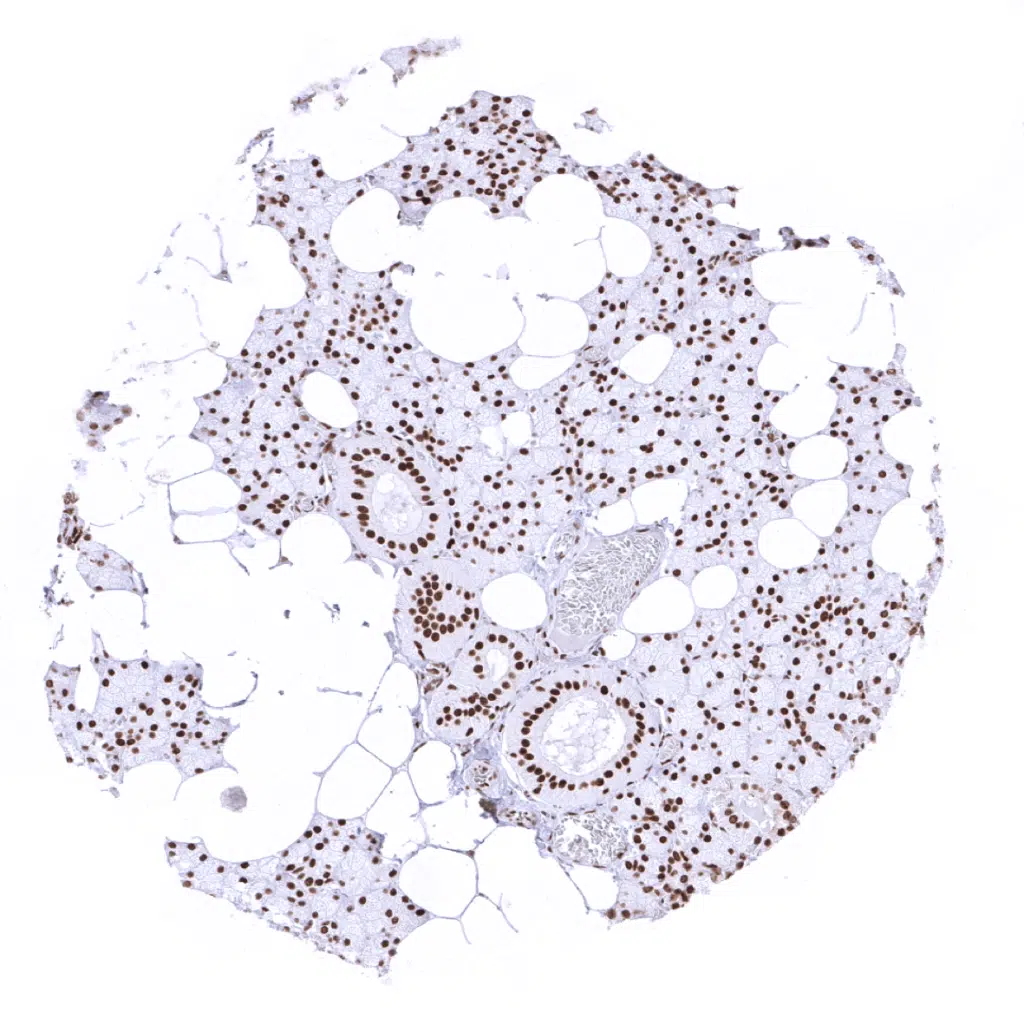

Testis